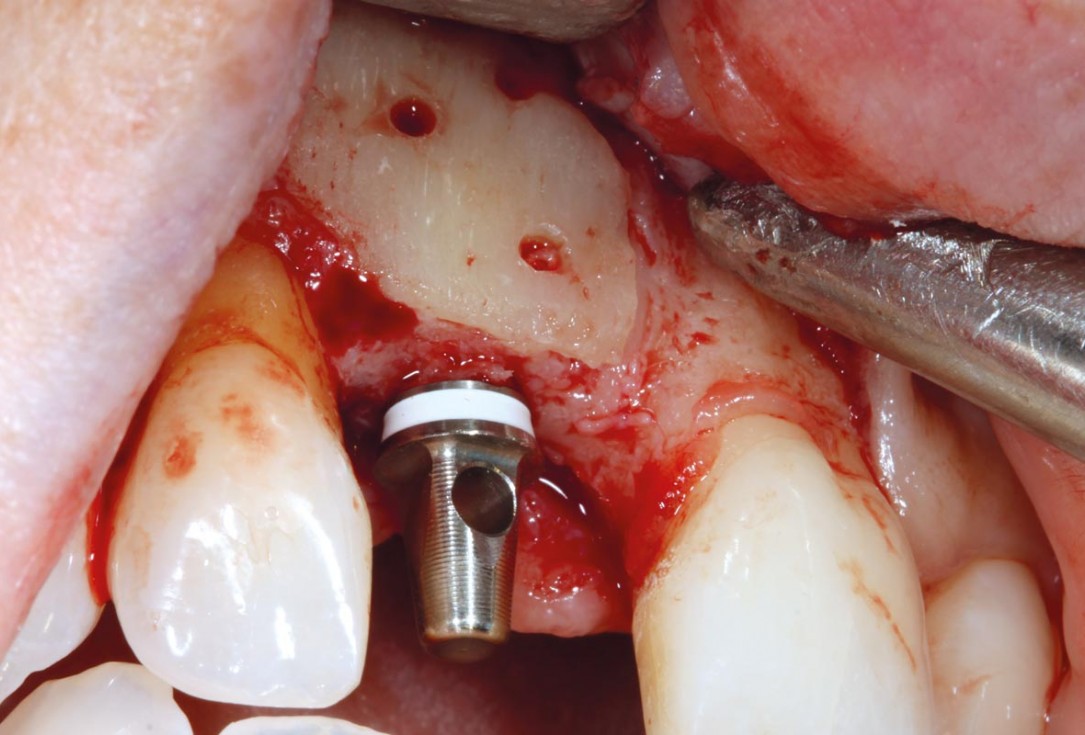

Bone defect in area 11-21 due to two lost implants (periimplantitis) after 15 years of function